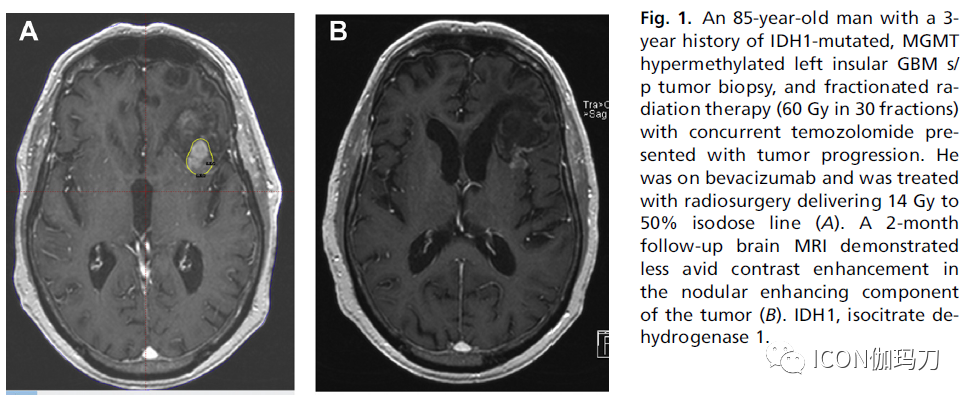

SRS可以使用多种方法完成,包括(1)伽玛刀放射外科(GKRS) (瑞典斯德哥尔摩Elekta Instruments AB),使用多个钴60伽玛辐射发射辐射束,(2)射波刀机器人放射治疗系统(美国加利福尼亚州Sunnyvale的Accuray);(3)带电粒子;(4)基于直线加速器的光子放射治疗。SRS通常在薄层T1w脑MRI上以单次分割的方式靶向钆剂增强肿瘤区域。当T1w图像不充分时,T2w /FLAIR MRI序列可用于定义细胞性增加的区域(图1),有试图提高SRS治疗GBM的体积,包括在对比增强的肿瘤巢以外的FLAIR高信号区域或通过对大体肿瘤体积添加5毫米的边缘扩展。

图1.一位85岁男性患者,左侧岛叶有IDH1突变、MGMT高甲基化GBM s/ p肿瘤活检史3年,出现肿瘤进展同步接受替莫唑胺和分割放射治疗(30次分割60Gy)。他服用贝伐单抗并接受放射外科治疗,给予14Gy至50%等剂量线(A)。2个月的随访脑部MRI显示肿瘤结节增强部分对比强化减弱;(B) IDH1异柠檬酸脱氢酶1。